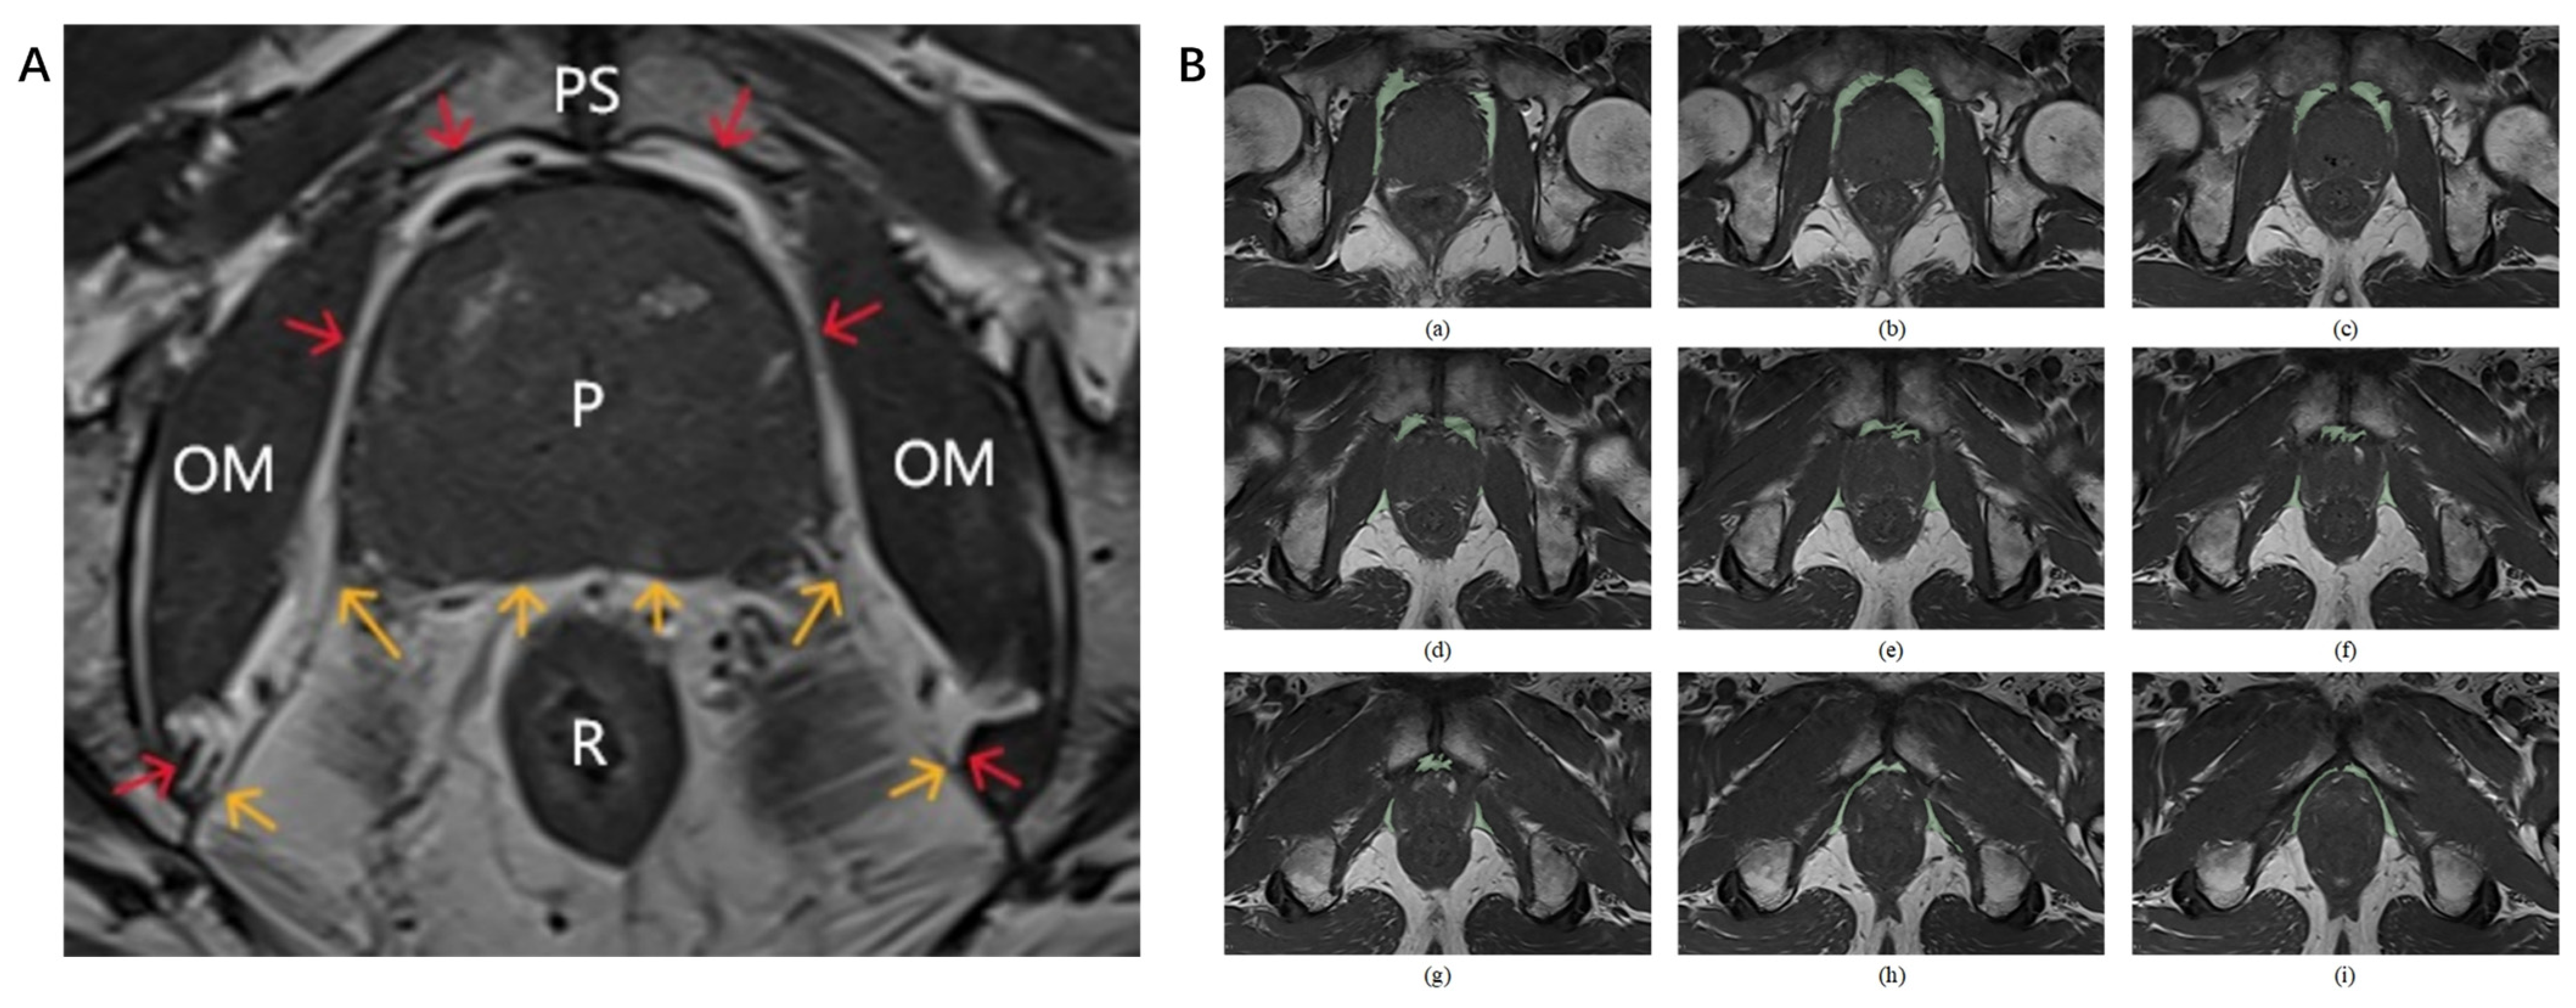

2.4.2. Delineation of PPAT Boundaries and Regions of Interest (ROIs) with Volume Calculation

2.4.3. Segmentation Consistency Validation

2.4.4. Extraction of Radiomic Features